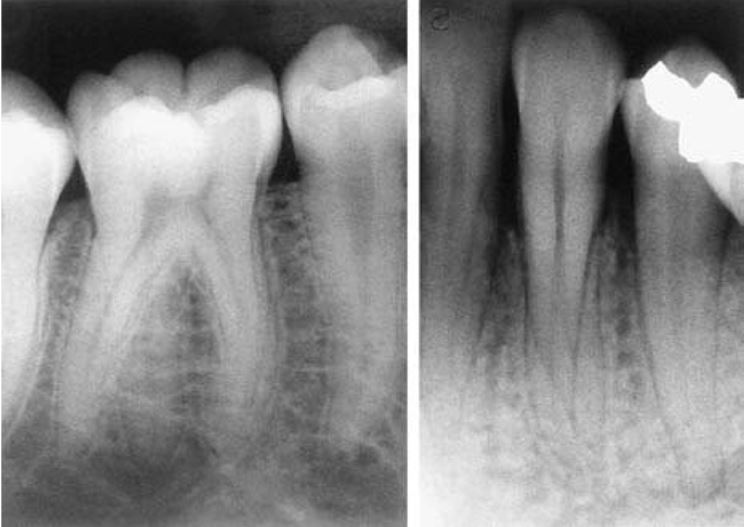

Răng dung hợp (fusion)

Xảy ra khi 2 mầm răng riêng rẽ nhập lại với nhau. Phần răng dung hợp thường chỉ chứa ngà và đôi khi chứa cả men.

Tỉ lệ gặp trên răng sữa cao hơn gấp 5 lần so với răng vĩnh viễn và thường xuất hiện cả hai bên hơn là một bên.

Răng thường bị ảnh hưởng nhiều nhất là các răng cửa. Răng dung hợp thường có một rãnh khá sâu chạy dọc theo mặt ngoài hoặc mặt trong và một khía ở rìa cắn tại vị trí mà 2 răng hợp lại. Trên phim X quang, răng dung hợp có 2 buồng tủy riêng biệt.

Răng sinh đôi (gemination)

Xảy ra khi một mầm răng có khuynh hướng chia thành 2 răng, nhưng sự phân chia này không hoàn toàn.

Tỉ lệ gặp ở răng sữa cao gấp 5 lần so với răng vĩnh viễn. Răng hay gặp nhất là răng cửa sữa hàm dưới và răng cửa vĩnh viễn hàm trên, bị một bên nhiều hơn hai bên.

Răng sinh đôi cũng hay có rãnh dọc theo mặt ngoài hoặc mặt trong, khía ở rìa cắn. Trên lâm sàng rất khó chẩn đoán phân biệt giữa răng dung hợp với răng sinh đôi.

Trên phim thì thấy răng sinh đôi chỉ có một buồng tủy rất rộng, chân răng to, thân răng chẻ đôi. Tuy vậy vẫn còn nhiều biến thể khác.